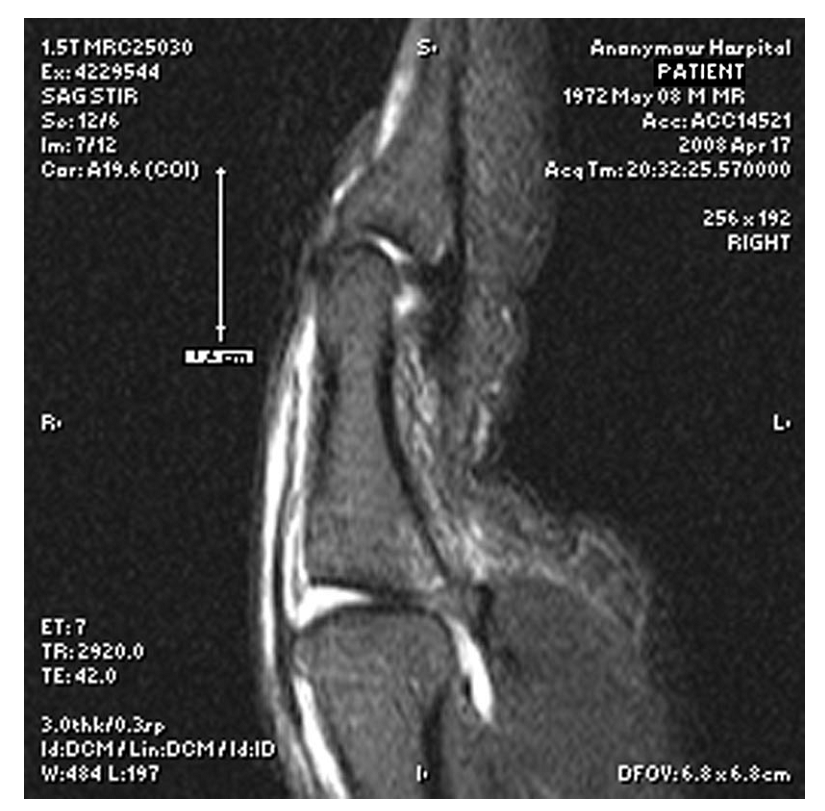

Magnetic Resonance Imaging (MRI):

As emphasized in the seed content, MRI is invaluable, especially for closed tendon injuries. It provides detailed visualization of the soft tissues, allowing for precise assessment of EPL tendon integrity, the extent of retraction of the proximal stump, and the presence of any intervening hematoma or scar tissue. This information directly influences the decision for surgery and helps plan the extent of surgical exploration.

The image above depicts a sagittal MRI view demonstrating significant EPL tendon retraction (white arrow) from its insertion, indicating a large gap between tendon ends. Such findings strongly advocate for surgical intervention due to the low probability of successful conservative management. - Ultrasound: Dynamic ultrasound can also be used to assess tendon retraction in real-time, although it is highly operator-dependent. It can differentiate between complete and partial tears and assess tendon excursion.